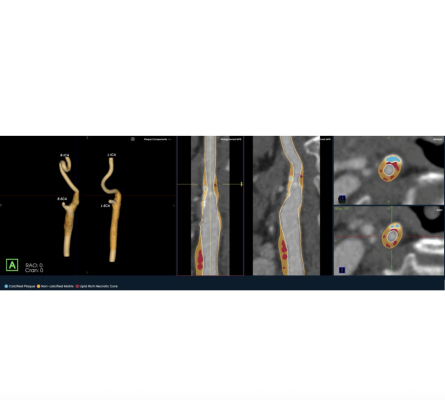

Photo: Elucid

Oct., 2025 — Elucid, an AI medical technology company focused on providing physicians with a more precise view of atherosclerosis, has introduced its PlaqueIQ image analysis software for the quantification and classification of plaque morphology in the carotid arteries. The first and only CT-based plaque analysis software indicated for the carotid vasculature, PlaqueIQ may help physicians diagnose carotid plaques at risk for rupture and develop patient-specific treatment pathways to prevent and monitor against ischemic stroke.

PlaqueIQ is the first and only FDA-cleared, non-invasive plaque analysis based on objective histology, offering physicians non-invasive CT Virtual Histology. PlaqueIQ delivers quantification and classification of plaque morphology and is uniquely capable of identifying and quantifying lipid rich necrotic core, the plaque type strongly linked with both cardiovascular and cerebrovascular risk.2,3,4

When used for both the coronary and carotid arteries, PlaqueIQ non-invasively delivers a quantitative and qualitative assessment of systemic atherosclerotic risk and creates the potential to perform both coronary and carotid plaque analysis in a single scan.